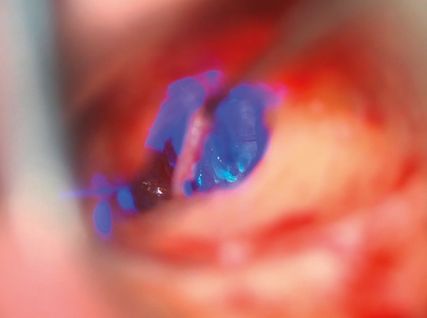

Die Therapie der Wahl stellt die operative Sanierung durch die Stapesplastik dar. Dabei wird der versteifte Stapes durch eine Protheseersetzt, die durch die perforierte oder teilentfernte Stapesfußplatte ins Innenohr ragt und am Incus fixiert wird. Im Laufe der Zeit haben sich Variationen der Operationstechnik ergeben und verschiedene Prothesenformen wurdenentwickelt. Die Wahl des Vorgehens und der Prothese hängt maßgeblich von den Vorlieben und der Praxis des Operateurs ab.10

In den Abbildungen 2–4 sind die Operationsschritte, wie sie in der Regel in unserer Klinik erfolgen, dargestellt.